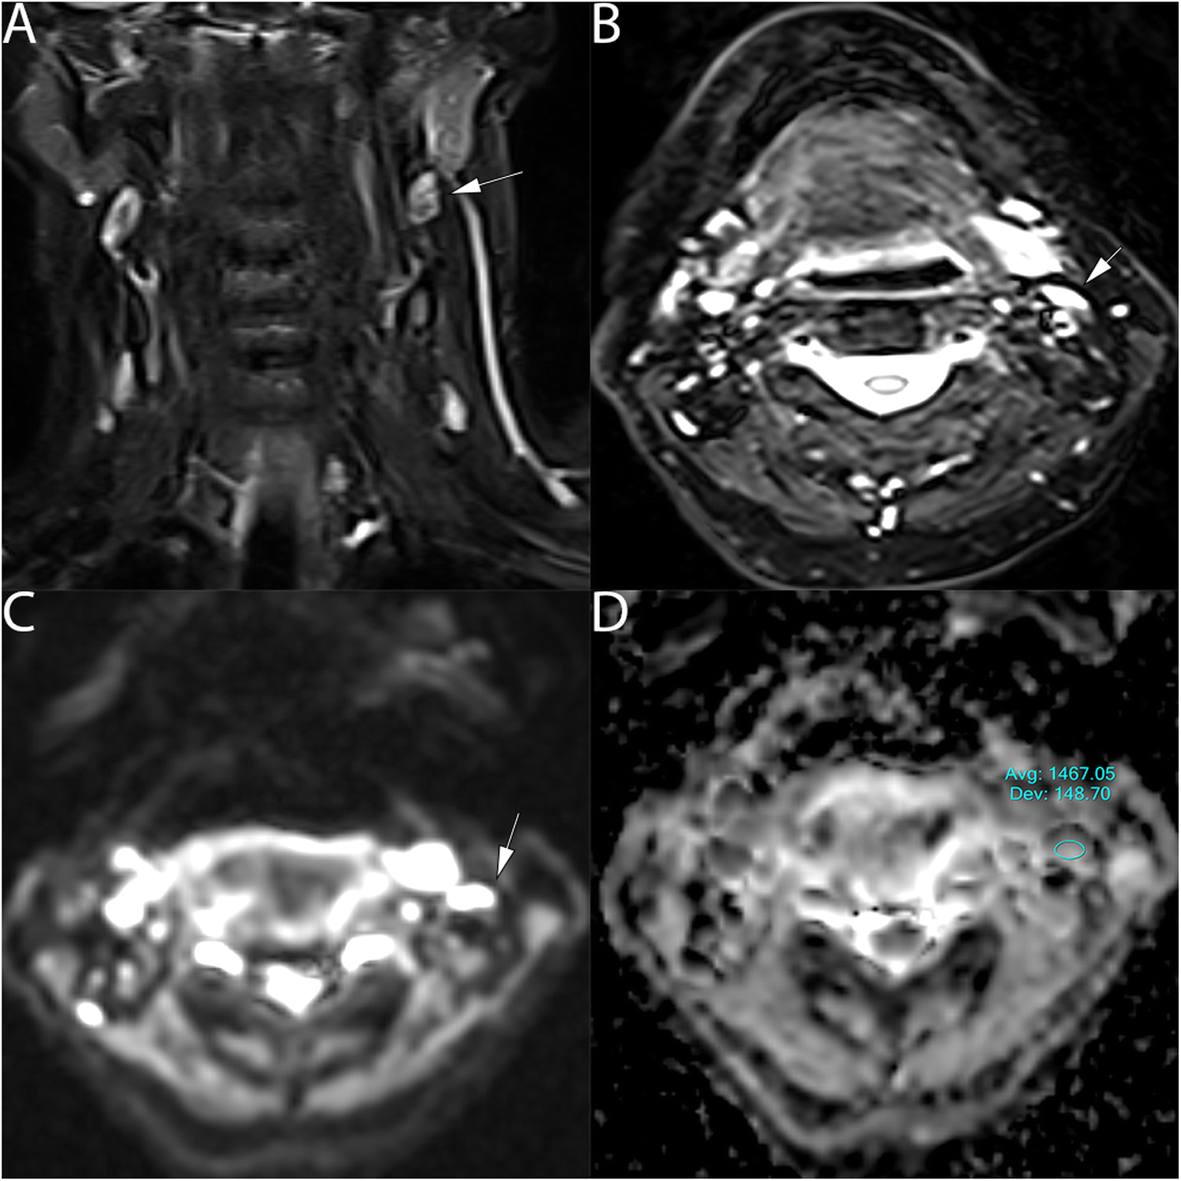

Fig. 4

61 years old healthy male with normal lymph node in the left side of the neck. a T2 coronal show normal lymph nodes (arrow). b T2 axial view shows the axial extension of the left lymph node, (5x7mm), (arrow). c DWI show high signal at b value 800mm2/s (arrow) and (d) the ADC map on the targeted lymph node show an ADC value of (1.467 ± 0.15*10− 3 mm2/s) (arrow)